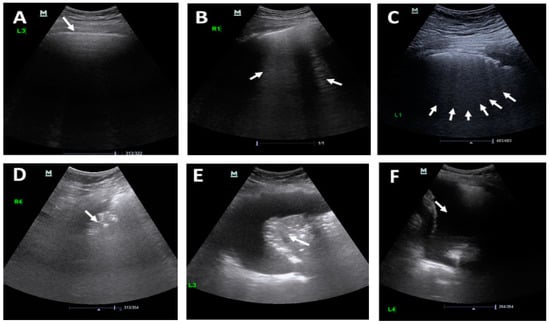

- Xing, C.; Li, Q.; Du, H.; Kang, W.; Lian, J.; Yuan, L. Lung ultrasound findings in patients with COVID-19 pneumonia. Crit. Care 2020, 24, 1–3. [Google Scholar] [CrossRef]

- Di Castelnuovo, A.; Bonaccio, M.; Costanzo, S.; Gialluisi, A.; Antinori, A.; Berselli, N.; Blandi, L.; Bruno, R.; Cauda, R.; Guaraldi, G.; et al. Common cardiovascular risk factors and in-hospital mortality in 3,894 patients with COVID-19: Survival analysis and machine learning-based findings from the multicentre Italian CORIST Study. Nutr. Metab. Cardiovasc. Dis. 2020, 30, 1899–1913. [Google Scholar] [CrossRef]